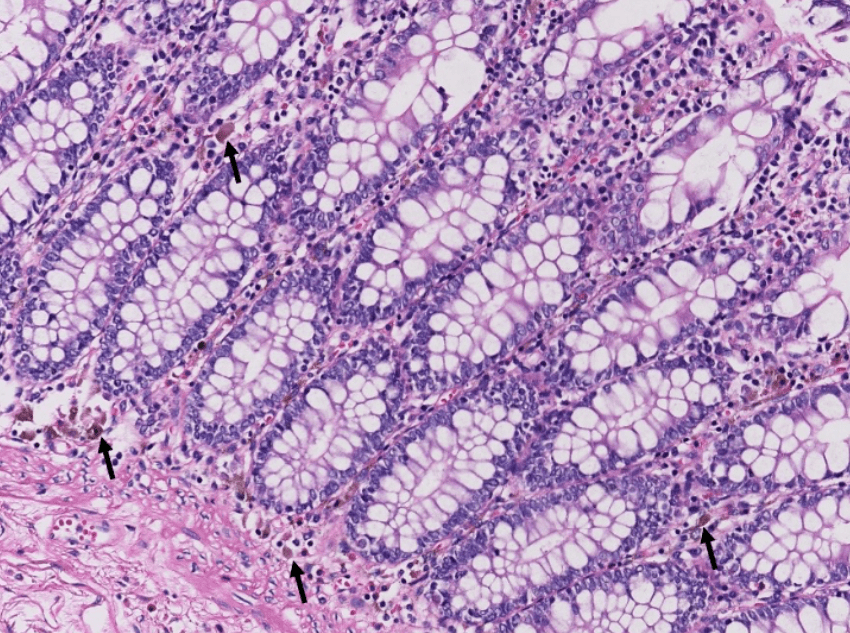

lung adenocarcinoma

colon cancer

endometrial cancer